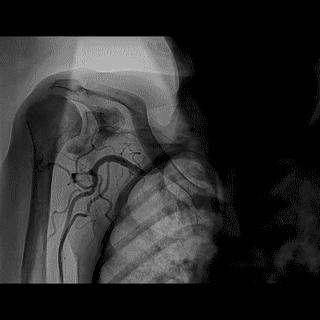

(4)LIMA桥血管造影

首选导管:JR4.0导管

其他导管:如果开口明显成角应选用专用的内乳动脉造影导管

➢ CASE 6

经股动脉途径TIG,非选择造影如果能清晰显影,可不做超选造影

➢ CASE 7

经左侧桡动脉途径JR4.0,非选择造影如果能清晰显影,可不做超选造影